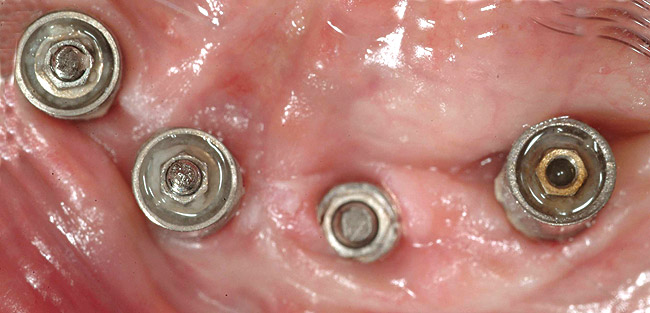

Figure 18  Occlusal view of four anterior maxillary implants with optimal peri-implant soft-tissue contours. Implant-level impressions of these implants were accomplished without incident.

Figure 18